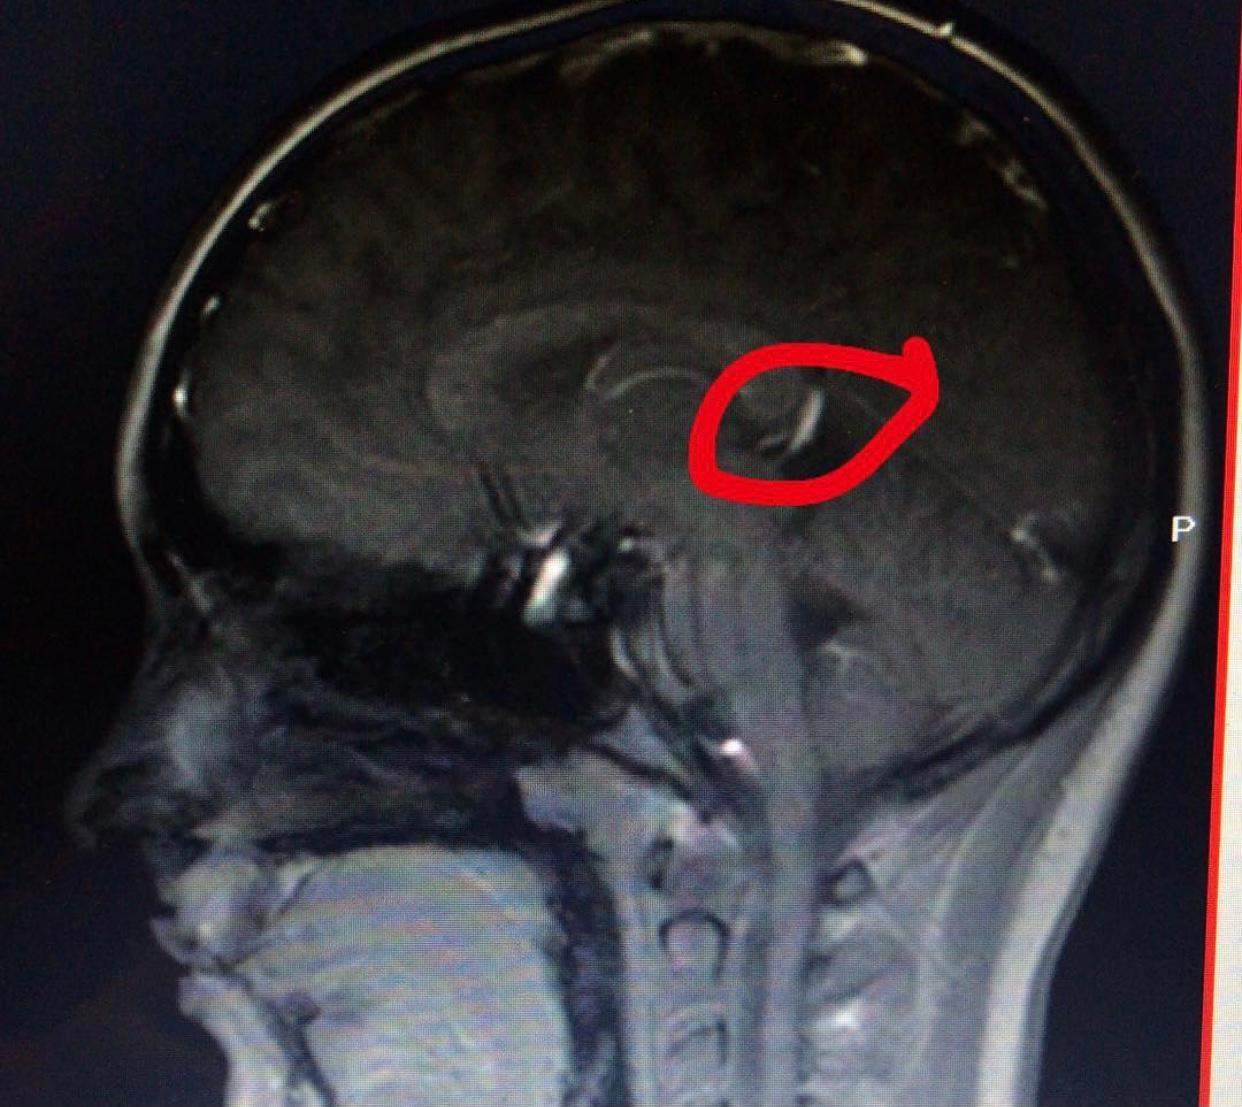

MRT Befund, MS, Multiple Sklerose werweisswas.de

Was sagt dieser MRTBefund vom Kopf aus? (Gesundheit und Medizin, Gesundheit, Medizin)

MRT Schädel, was ist das? (MRT Befund, Kontrastmittel)